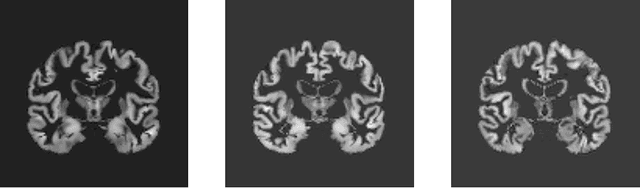

Abstract:Although convolutional neural networks (CNN) achieve high diagnostic accuracy for detecting Alzheimer's disease (AD) dementia based on magnetic resonance imaging (MRI) scans, they are not yet applied in clinical routine. One important reason for this is a lack of model comprehensibility. Recently developed visualization methods for deriving CNN relevance maps may help to fill this gap. We investigated whether models with higher accuracy also rely more on discriminative brain regions predefined by prior knowledge. We trained a CNN for the detection of AD in N=663 T1-weighted MRI scans of patients with dementia and amnestic mild cognitive impairment (MCI) and verified the accuracy of the models via cross-validation and in three independent samples including N=1655 cases. We evaluated the association of relevance scores and hippocampus volume to validate the clinical utility of this approach. To improve model comprehensibility, we implemented an interactive visualization of 3D CNN relevance maps. Across three independent datasets, group separation showed high accuracy for AD dementia vs. controls (AUC$\geq$0.92) and moderate accuracy for MCI vs. controls (AUC$\approx$0.75). Relevance maps indicated that hippocampal atrophy was considered as the most informative factor for AD detection, with additional contributions from atrophy in other cortical and subcortical regions. Relevance scores within the hippocampus were highly correlated with hippocampal volumes (Pearson's r$\approx$-0.81). The relevance maps highlighted atrophy in regions that we had hypothesized a priori. This strengthens the comprehensibility of the CNN models, which were trained in a purely data-driven manner based on the scans and diagnosis labels. The high hippocampus relevance scores and high performance achieved in independent samples support the validity of the CNN models in the detection of AD-related MRI abnormalities.

Abstract:Deep Neural Networks - especially Convolutional Neural Network (ConvNet) has become the state-of-the-art for image classification, pattern recognition and various computer vision tasks. ConvNet has a huge potential in medical domain for analyzing medical data to diagnose diseases in an efficient way. Based on extracted features by ConvNet model from MRI data, early diagnosis is very crucial for preventing progress and treating the Alzheimer's disease. Despite having the ability to deliver great performance, absence of interpretability of the model's decision can lead to misdiagnosis which can be life threatening. In this thesis, learned shape features and abstractions by 3D ConvNets for detecting Alzheimer's disease were investigated using various visualization techniques. How changes in network structures, used filters sizes and filters shapes affects the overall performance and learned features of the model were also inspected. LRP relevance map of different models revealed which parts of the brain were more relevant for the classification decision. Comparing the learned filters by Activation Maximization showed how patterns were encoded in different layers of the network. Finally, transfer learning from a convolutional autoencoder was implemented to check whether increasing the number of training samples with patches of input to extract the low-level features improves learned features and the model performance.

Abstract:Convolutional neural networks (CNN) have become a powerful tool for detecting patterns in image data. Recent papers report promising results in the domain of disease detection using brain MRI data. Despite the high accuracy obtained from CNN models for MRI data so far, almost no papers provided information on the features or image regions driving this accuracy as adequate methods were missing or challenging to apply. Recently, the toolbox iNNvestigate has become available, implementing various state of the art methods for deep learning visualizations. Currently, there is a great demand for a comparison of visualization algorithms to provide an overview of the practical usefulness and capability of these algorithms. Therefore, this thesis has two goals: 1. To systematically evaluate the influence of CNN hyper-parameters on model accuracy. 2. To compare various visualization methods with respect to the quality (i.e. randomness/focus, soundness).